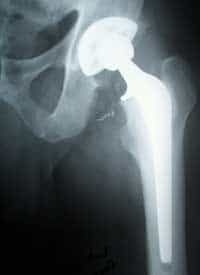

Con gli anni, ma non solo, le articolazioni perdono elasticità e si possono verificare fenomeni di artrosi che provocano dolore, fino ad una scarsa mobilità del paziente. In questi casi si ricorre alla protesi d’anca simile a quella visibile nella radiografia qui a lato. L’intervento in se è abbastanza semplice e dura circa un’ora. La fase più delicata e complicata è la progettazione dell’intervento stesso, nella quale si deve calcolare la giusta posizione e inclinazione della protesi che andrà a sostituire l’osso. La pianificazione viene fatta basandosi su delle radiografie a cui vengono sovrapposti dei lucidi con le varie protesi disponibili per trovare la misura più adatta. Un errore di valutazione in questa fase potrebbe comportare un’angolazione della protesi errata, il che si tradurrebbe in una camminata anormale del paziente una volta dimesso. Per la sostituzione totale dell’articolazione dell’anca si utilizzano protesi in lega di titanio non cementate, che permettono al paziente di tornare a camminare già dopo 3 o 4 giorni al massimo dall’intervento. Inoltre, la non cementificazione dell’impianto è un pregio perchè le colle polimeriche utilizzate sono altamente tossiche e provocano necrosi. [Proseguendo nell’articolo, vengono illustrate tutte le fasi principali dell’intervento e per loro natura non sono adatte a persone “sensibili”]

Sopra una protesi in lega di titanio. Da notare la parte “ruvida” del gambo che promuove l’osteointegrazione dell’impianto. A questo punto si riportano i dati, ottenuti precedentemente nella fase preoperatoria, con un pennarello sulla gamba del paziente.